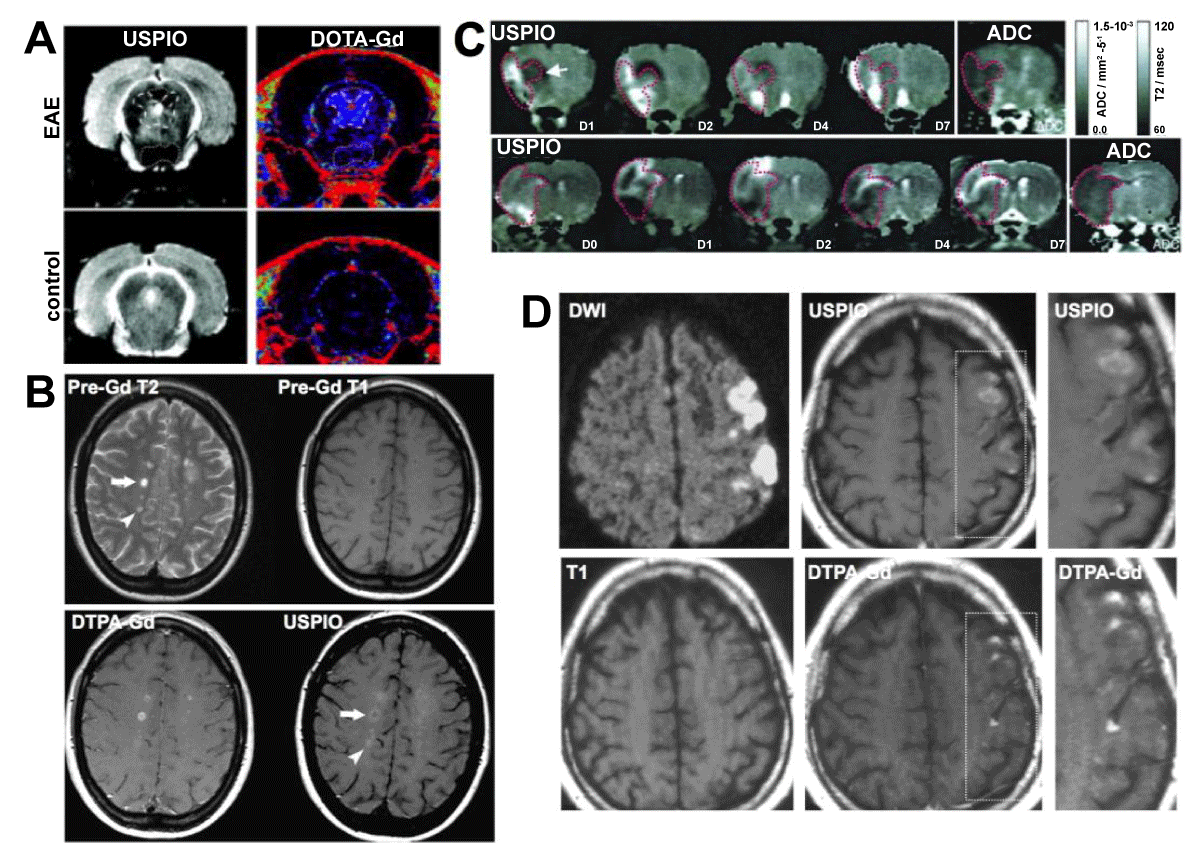

| Figure 8: Imaging of phagocytic cells with iron oxide-enhanced MR imaging. (A) USPIO and DOTA-Gd-enhanced MR imaging of EAE rats. A periventricular lesion shows DOTA-Gd enhancement but not USPIO uptake. Vice versa, a ventral lesion shows USPIO uptake but no DOTA-Gd enhancement. No enhancement is seen in a control animal. (B) Pre-Gd T2 MRI on a MS patient demonstrates multiple lesions, and while there is a DTPA-Gd and USPIO enhancing lesions (arrow), there also is an USPIO-uptake-only lesion (arrowhead). (C) Spatiotemporal profile of USPIO uptake in the ischemic rat brain over 7 days. While USPIO uptake is first seen in the periphery of the infarct (ADC map), uptake becomes more central on the following days, while no uptake is seen on day 7. (D) Comparison of USPIO and DTPA-Gd in a patient with ischemic stroke. Diffusion-weighted imaging displays ischemic area. Areas of USPIO uptake are clearly different from gadolinium enhancement. (Modified from Rausch et al. [10,171], Vellinga et al. [166] and Saleh et al. [173] with permission.) |